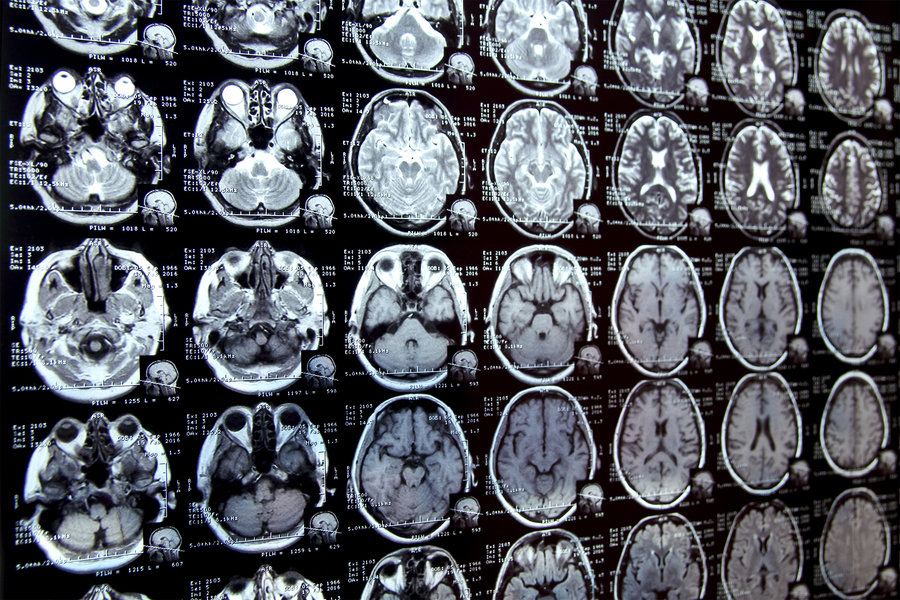

Caption:MIT researchers have developed a new AI-based tool that rapidly annotates areas of interest in medical images and can help in the study of new treatments or map disease progression. Image credit: iStock

Annotating regions of interest in medical images, a process known as segmentation, is often one of the first steps clinical researchers take when running a new study involving biomedical images.

For instance, to determine how the size of the brain’s hippocampus changes as patients age, the scientist first outlines each hippocampus in a series of brain scans. For many structures and image types, this is often a manual process that can be extremely time-consuming, especially if the regions being studied are challenging to delineate.